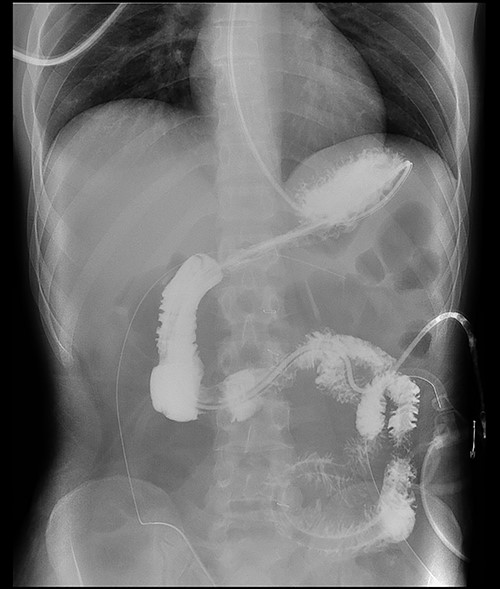

Here, we report a case of a 21-year-old man who was admitted to our hospital following a motor vehicle collision where he was a pedestrian, hit by a car and pushed against the bumper of another car. Upon arrival to the hospital, he was conscious and oriented, with normal vital signs. Abdominal examination revealed ecchymosis over the epigastric area with tenderness, however, no distention was noticed. Focused assessment with sonography for trauma result was positive in the right upper quadrant. His initial blood test results revealed a white blood cell (WBC) count of 26.5 × 109 cells/l and a hemoglobin level of 150 g/l. His serum amylase and lactic acid levels were 92 U/l and 4.53 mmol/l, respectively. His base deficit was 4.3. He underwent abdominal computed tomography (CT) with oral contrast, which showed query duodenal and possible pancreatic transection with active arterial extravasation (Figs 1–3). In addition, CT revealed a comminuted right intertrochanteric femoral fracture without associated vascular injury.

Exploratory laparotomy was performed, which revealed ~500 ml of blood in the peritoneal cavity, central retroperitoneal hematoma, peripancreatic hematoma and complete transection of the third part of the duodenum. The retroperitoneal hematoma and peripancreatic hematoma were nonexpanding. A formal end-to-end anastomosis of the third part of the duodenum was performed using 3–0 polydioxanone (PDS) in a single layer. Double decompression of the duodenum was achieved using a nasoduodenal tube (ND) and a retrograde duodenostomy tube. A jejunostomy tube was created for feeding as well.

Postoperatively, the ND and retrograde duodenostomy tubes were maintained on continuous suction. Feeding through jejunostomy tube was initiated on postoperative Day 2, and the ND tube was removed on postoperative Day 23 when oral feeding was initiated. Although postoperative CT and Gastrografin swallow confirmed good anastomosis without evidence of leaks (Figs 4–7), The prolonged hospital stay and the delays in removing ND tube and initiation of the oral intake was because of persistent sepsis and high WBC counts, which was later confirmed to be secondary to abscess in his right thigh.